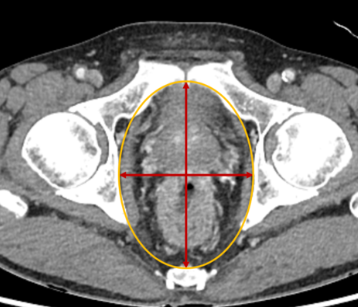

골반수술은 복잡한 해부학적 구조 때문에 높은 위험성을 가지고 있습니다. 특히, 합병증 발생률이 최대 75%로 보고되며, 섬망과 폐렴 같은 문제는 고령 환자에게서 더 흔하게 발생합니다.

수술 과정에서 발생하는 합병증도 무시할 수 없습니다. 혈관 손상이나 요관 손상과 같은 문제는 수술의 정확도와 직접적으로 관련됩니다. 정확한 진단과 숙련된 의료진의 참여가 무엇보다 중요합니다.

골반수술은 다양한 질환과 상태를 해결하기 위해 시행됩니다. 자궁암, 난소낭종, 골반장기탈출증 등의 질환에 따라 적합한 수술 방법이 선택됩니다.

배뇨 및 배변 장애는 골반 부위의 신경 손상으로 인해 나타날 수 있습니다. 이를 예방하기 위해서는 수술 전 정밀 진단이 중요합니다.